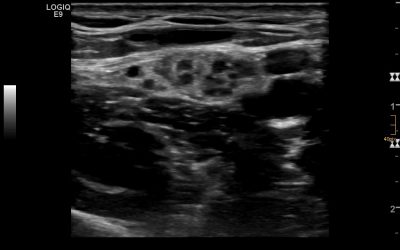

Ultrasound of nerves does have some special requirements as we are assessing small to very small structures. While “bigger” nerves like the median or ulnar nerve present with cross-sectional areas (CSA) from 8 to 15 mm2 and do therefore not impose a major problem in...